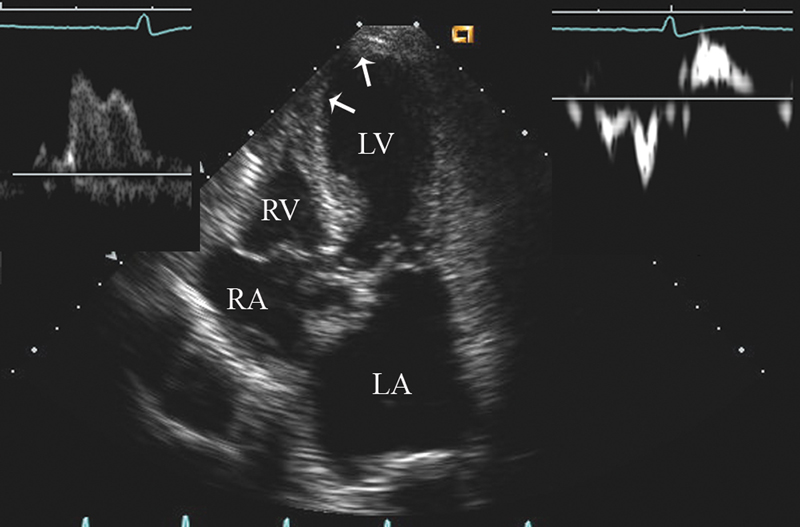

فحوصات تشخيصية لبعض امراض القلب والشرايين التاجية